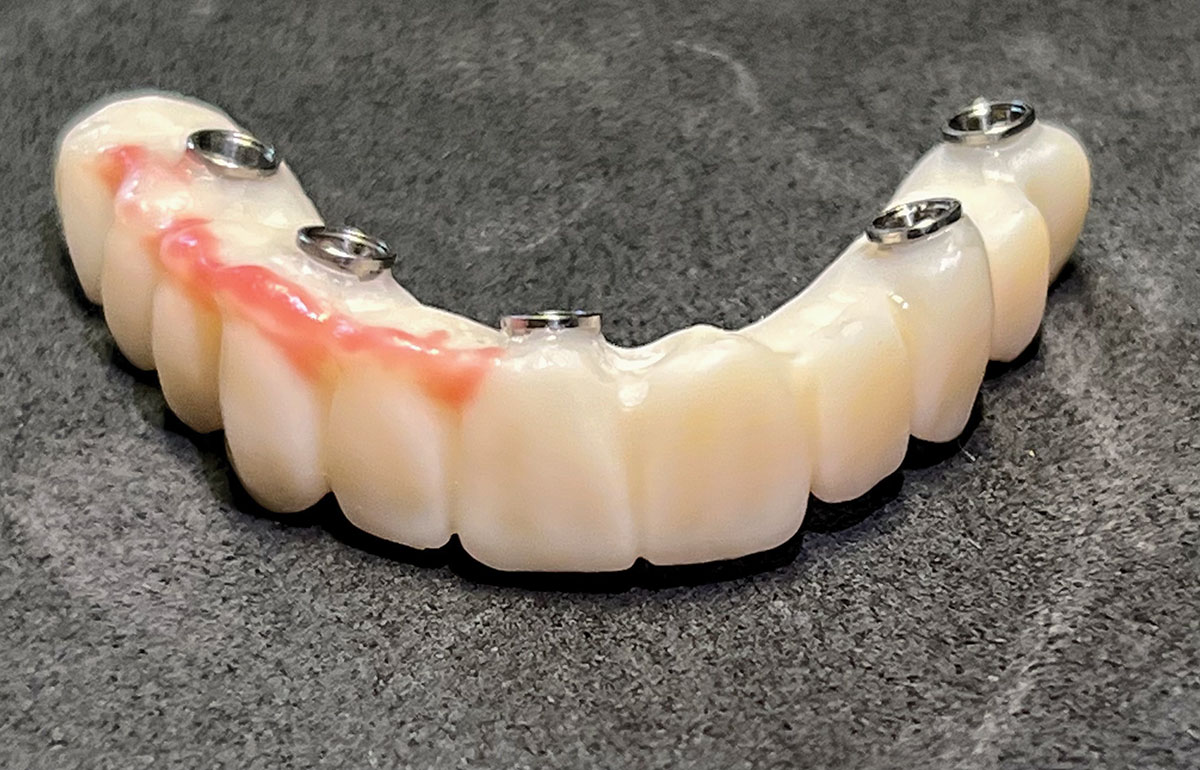

The implant company then returned an STL design file electronically via email. The office staff sent this file to the practice's 3D printer, and the appropriate color nanoceramic resin was used to print the prosthesis at 100 microns. Next, metal titanium (ti)-base cylinders, made specifically for the multi-unit abutments, were inserted into the prosthesis, which was then stained and glazed, and gingival color was applied to establish optimum esthetics (Figure 5).

Fig 5. Maxillary provisional prosthesis printed and ti-bases inserted.

Figure 5